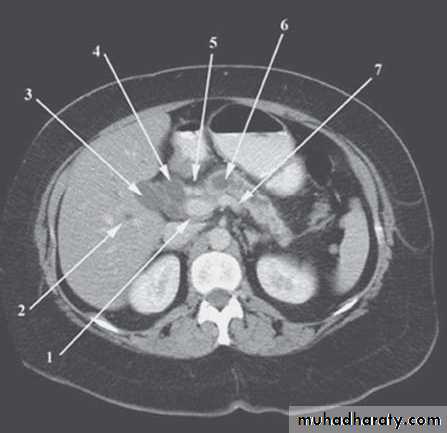

CT scan;

limited useful in investigating the biliary treeOnly when there is a possibility of cancer of gall bladder or bile ducts

Use of CT scan is an integral part of the differential diagnosis of obstructive jaundice